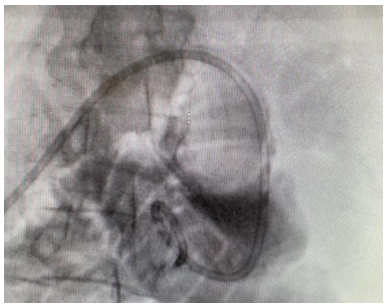

The patient is a 48-year-old male who was diagnosed with metastatic pancreatic cancer in November 2023. The primary cancer was from the body of the pancreas with metastatic disease to the liver and lymph nodes. He developed severe duodenal obstruction and was unable to eat or drink. The CT scan showed obstruction at the duodenojejunal junction. The computed tomography showed upstream dilation of the stomach and duodenum (Figures 1 and 2). He was evaluated for EUS-GE.

Figure 2. Distended duodenum and stomach due to obstruction